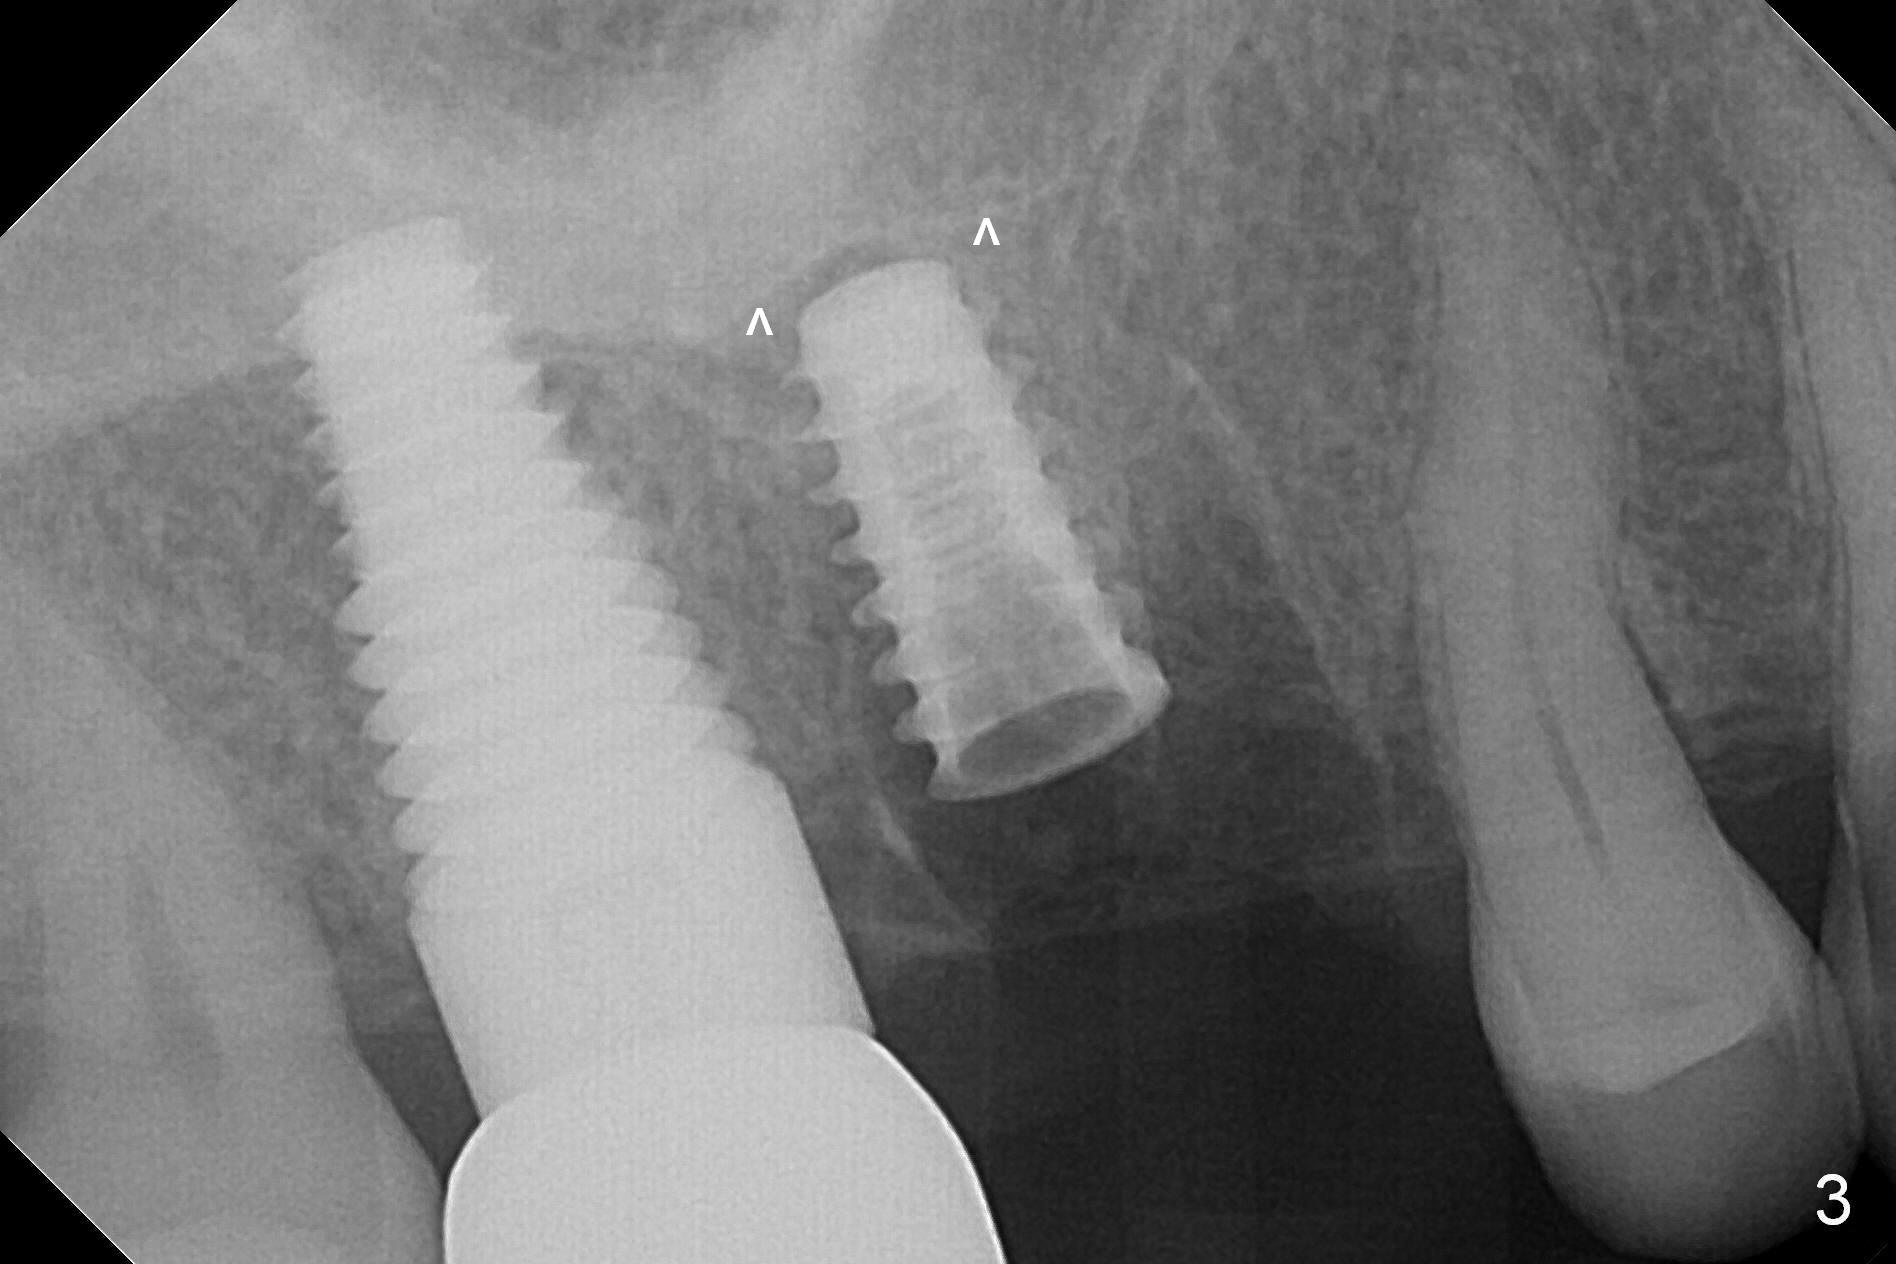

Heavy bruxism is characterized by the crack at #3 (symptomatic, requiring emergency extraction) and loss of the palatal cusp at #5 (Fig.1). Osteotomy is initiated in the septal slope (Fig.2 S) with a 1.6 mm pilot drill for 9 mm (with sudden empty feeling), followed by Marking bur. After 4.3 mm Magic Drill is used for ~ 9 mm, the sinus membrane is found to perforate. A dummy implant (5x9 mm, 2 mm shorter than design) is placed short of the sinus floor (Fig.3 ^). Prior to placement of 5.5x9 mm IBS implant (~ 35 Ncm, Fig.4,5), a piece of Osteogen plug is inserted into the osteotomy for repair of the perforation. The final implant is also shy of the sinus floor (Fig.5 ^). The Osteogen plug is apparently placed underneath the sinus floor so that it should be able to repair hard and soft tissue defects. The remaining sockets are mainly filled with Osteogen plug, while the implant plateau is covered by autogenous bone and Osteogen. When a 6.5x4(3) mm abutment is placed, an immediate provisional is fabricated (Fig.6) with its margin placed subgingival (Fig.6 inset dashed line). This innovative design of the provisional is to prevent collapse of the most coronal gingiva and loss of bone graft, particularly where the bony plate is defective. Although there is mild pain postop, nasal hemorrhage or discharge is absent.